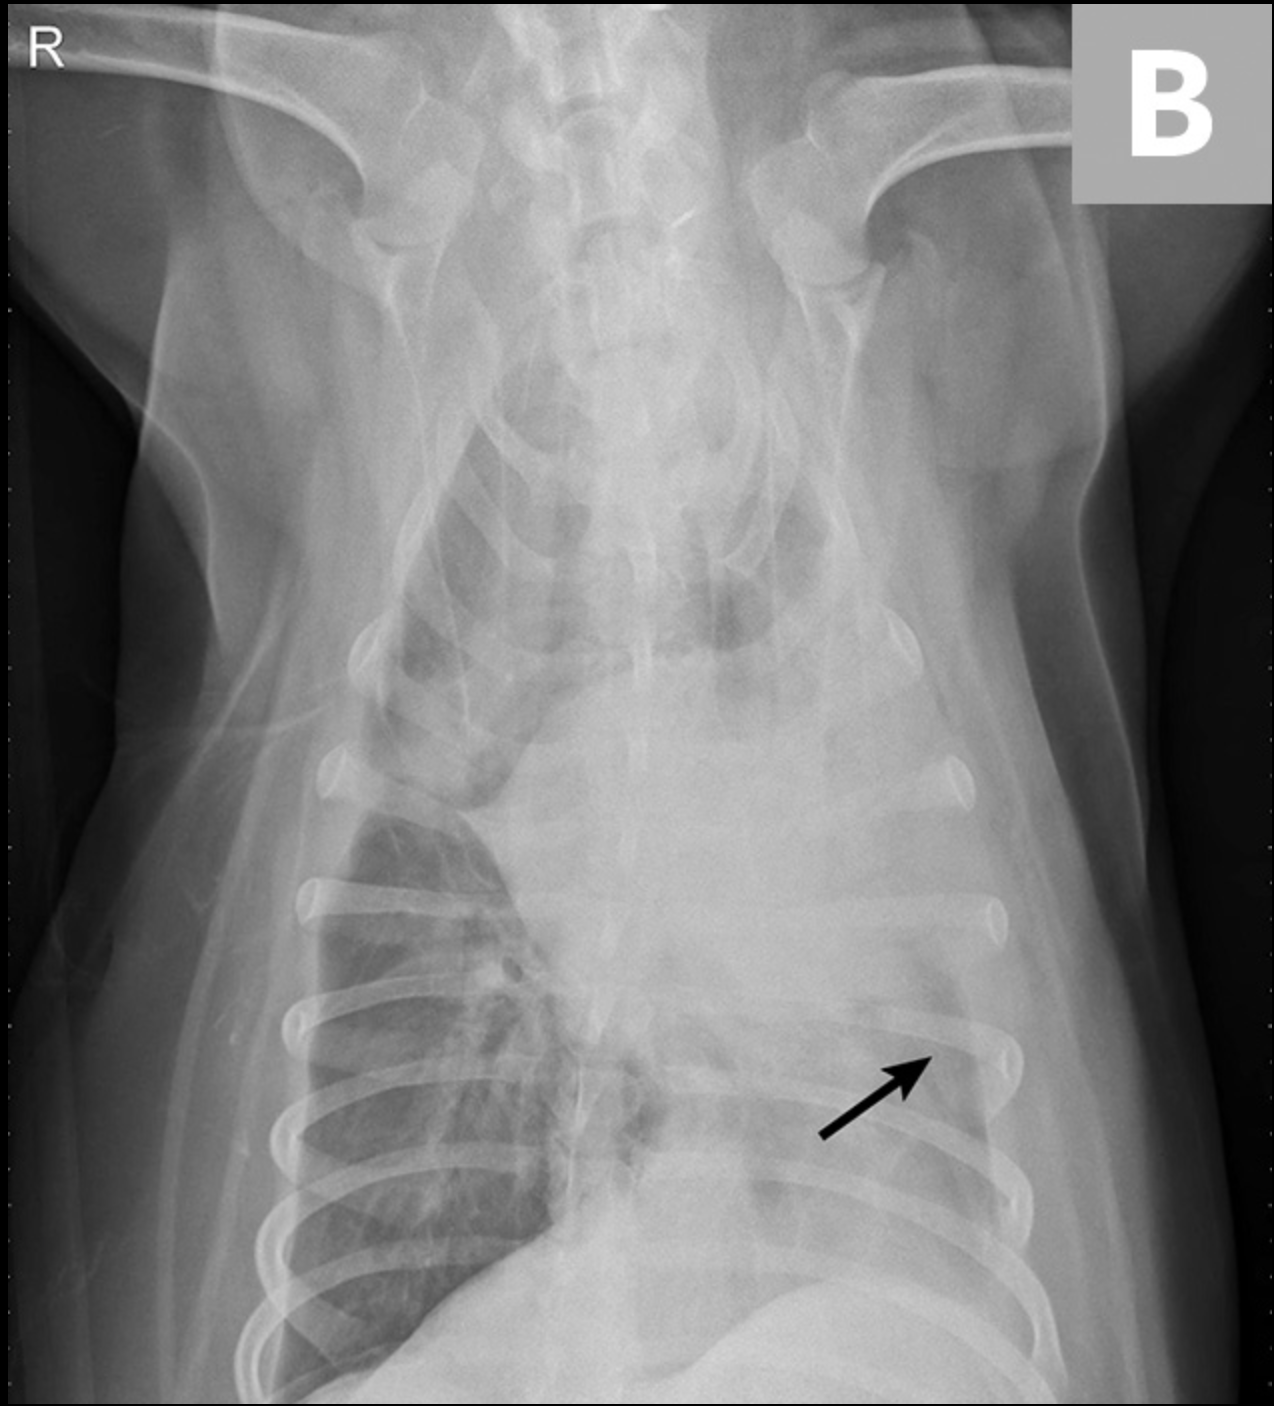

Las radiografías obtenidas después de la toracocentesis demostraron un derrame pleural mejorado y la consolidación del lóbulo medio izquierdo del pulmón (Figura 3). Basado en el abultamiento de los tejidos blandos cerca del hilio y el broncoramón de aire que se extiende cranealmente, el diferencial primario fue la torsión del lóbulo pulmonar (LLT). Otras consideraciones incluyen masa pulmonar, absceso o granuloma.